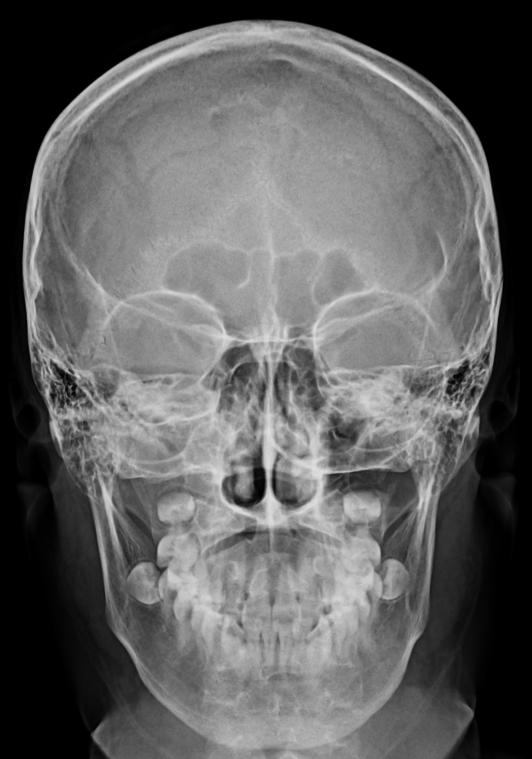

Skull AP (머리뼈 전후방향 촬영)

- supine(누운자세) 혹은 erect(선 자세)를 취한다

- OML(Orbito meatal Line, 외안각과 외이도를 잇는 선)이 카세트와 수직이 되게 한다.

- 촬영 전 귀걸이 목걸이 등 이물질을 제거한다.

- 수정체에 대한 피폭을 고려해 AP가 아닌 PA도 가능하다.

- 부비동이 목적이라면 caldwell 방법이 더 좋다.

- PA에 비해 AP가 얼굴뼈 확대가 있다.

- 비근점(nasion)을 향해 수직입사 한다.

- 100cm

- 75KvP / 14mAs

- Grid(+)

- 안와(Orbit) 1/3지점에 petrous ridge가 보여야 한다.

- 영상 좌우가 대칭되어야 한다.